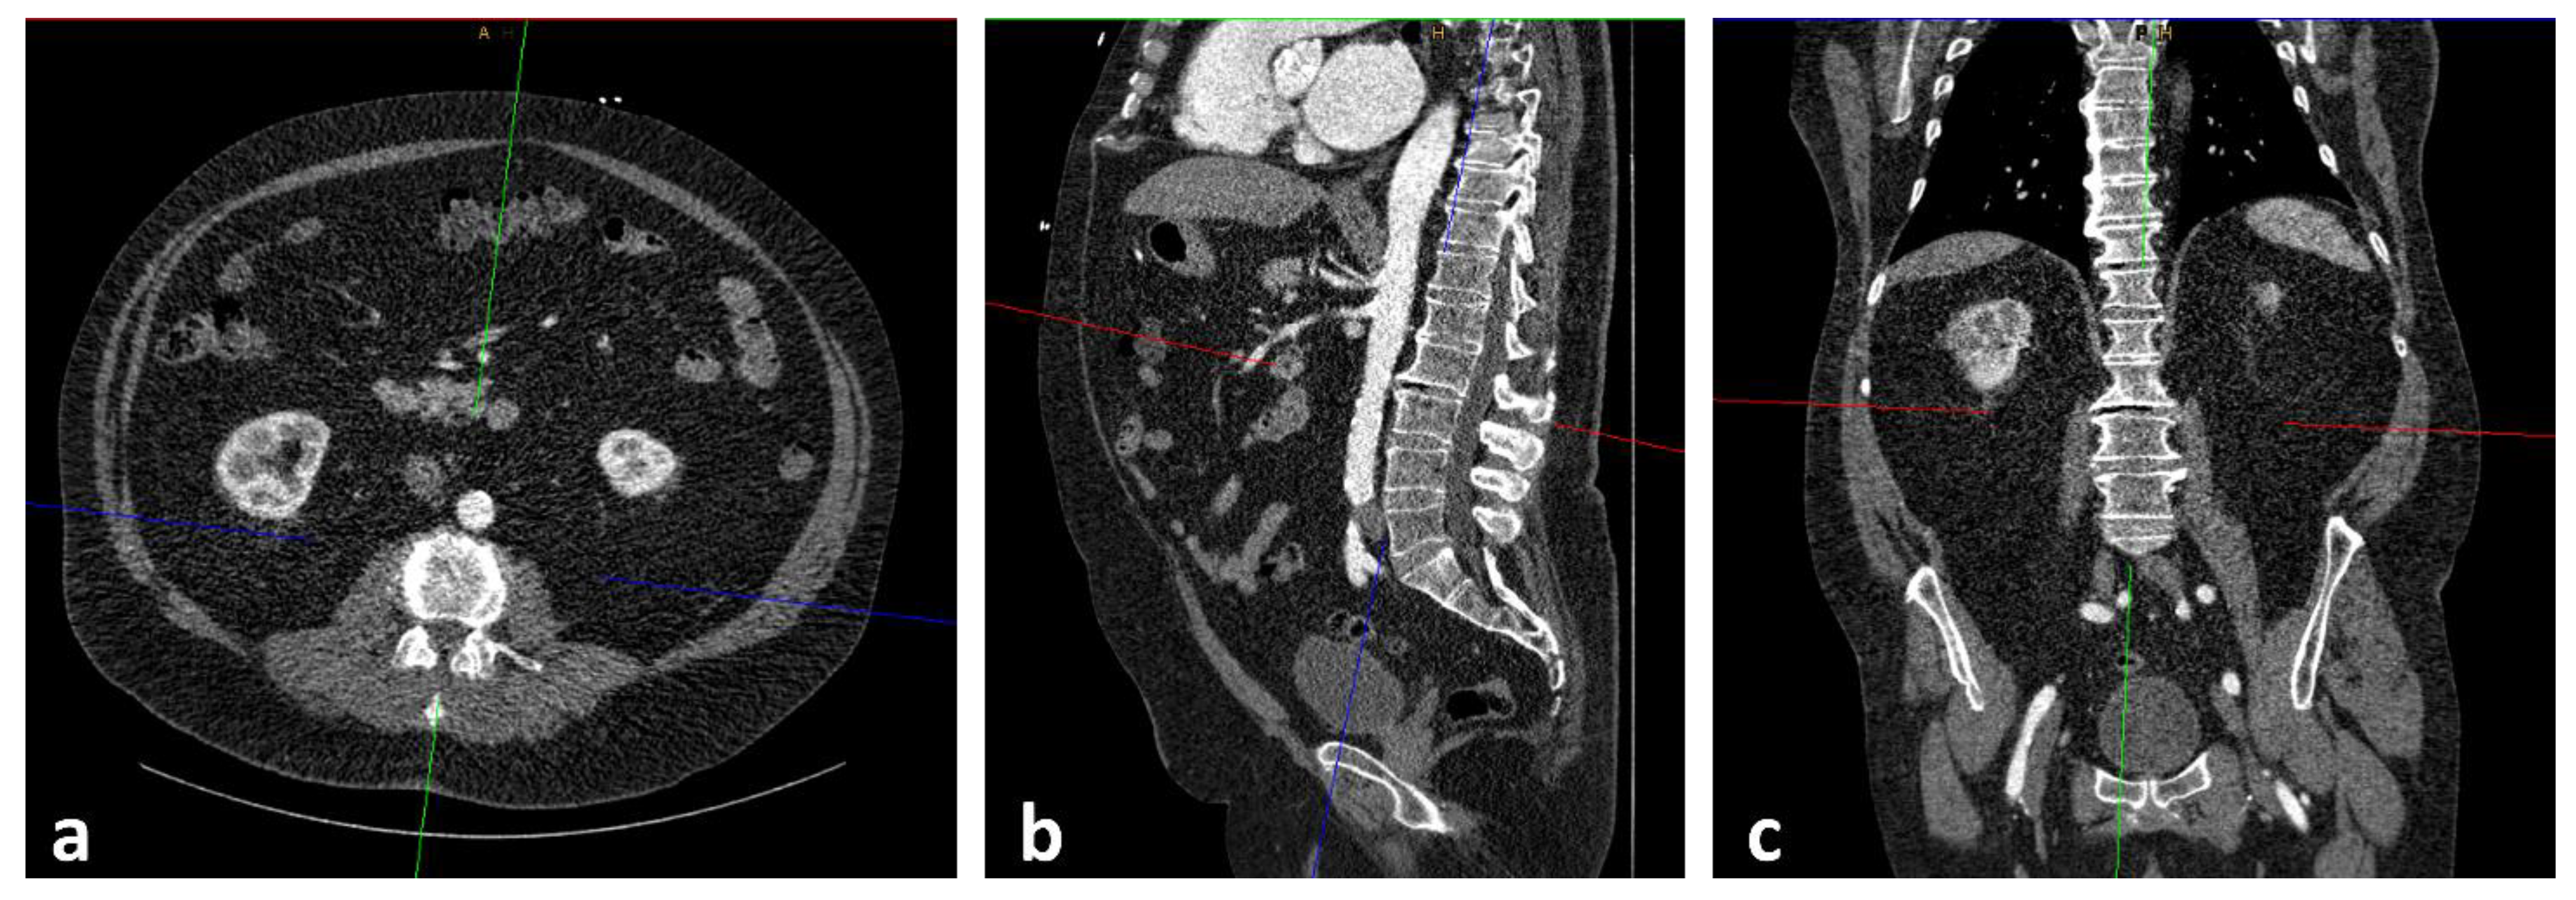

At both cardiological centers, patients received a pre-interventional, ECG triggered CT-angiography (CTA) of the entire aorta including the femoral arteries in order to assess, among others, aortic annulus size, aortic, coronary and general vascular anatomy and vascular access side for routine diagnostic workup. Two radiologists, one board certified with seven years of experience in vascular imaging (radiologist 1) and the other in the fourth year of training (radiologist 2), independently assessed the psoas muscle area (PMA: mm2). The radiologists were blinded to all clinical and laboratory data. Measurements were obtained on axial CTA scans of the entire aorta performed on a multidetector CT scanner with a patient size-adapted tube voltage (80–120 kVp) and active tube current modulation. A bolus-tracking technique was applied with a 100 mL bolus of non-ionic iodinated contrast media followed by 70 mL saline solution injected at a flow rate of 3.5–5 mL/s. Imaging data were analyzed using a soft tissue kernel with a slice thickness of 3 mm and a reconstruction interval of 2 mm. PMA was measured in all patients at the level of the superior endplate of the third lumbar vertebrae (L3) by manually outlining the right and left psoas muscles (Figure 1 and Figure 2). The total area of the psoas muscle was obtained by adding the areas of the left and right psoas muscles. Normalization to body surface area (BSA) yielded the indexed PMA (PMAi: mm2/m2). Measurements were performed on a picture archiving and communication system (PACS, Workstation, Impax; Agfa, Mortsel, Belgium).

Figure 1.

Process of slice selection using the Extended Multiplanar Reconstruction Plugin in IMPAX. The axial slice (a) was aligned parallel to the superior endplate of the third lumbar vertebrae at sagittal (b) and coronal (c) reconstructions.